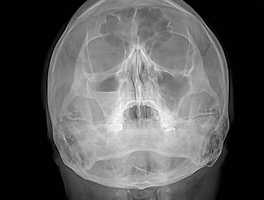

| Rt. maxillary sinusitis (0) | 2018.10.05 |